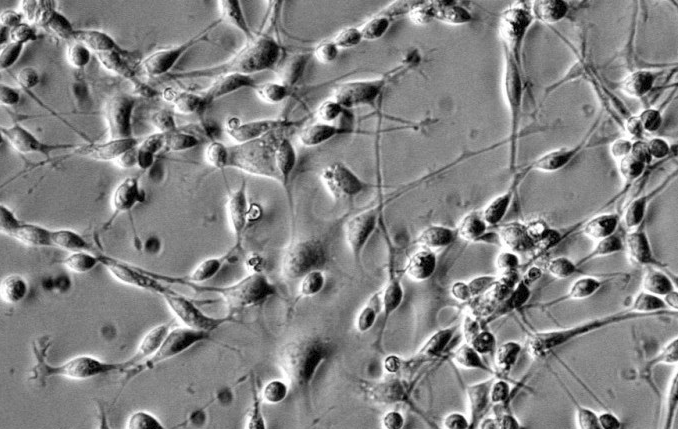

来自ScienCell研究实验室的HOPC是从人脑中分离出来的。HOPC在纯化后冷冻保存并冷冻。每个小瓶含有>1×10^6个细胞,1ml体积。HOPC的特征在于用对A2B5和O4特异的抗体的免疫荧光。HOPC对HIV-1,HBV,HCV,支原体,细菌,酵母和真菌均为阴性。HOPC保证在ScienCell研究实验室提供的条件下进一步培养; 但是,HOPC不推荐用于扩增或长期培养,因为细胞不会在培养中增殖。

少突胶质细胞的前体细胞初是由Raff,Miller和Noble在1993年发现的[1]并且已经被广泛研究。这些前体细胞在文献中称为少突胶质细胞型2星形胶质细胞祖细胞或少突胶质细胞前体细胞(OPC)。发育中和成人中枢神经系统都含有OPC [2,3]。少突胶质细胞是中枢神经系统的髓鞘形成细胞,由OPC发展而来。在培养中,OPC可以在碱性成纤维细胞生长因子存在下从神经祖细胞或神经干细胞产生,并且它们在血小板衍生的生长因子或由星形胶质细胞产生的因子的存在下增殖[4]并分化成成熟的少突胶质细胞。基于这些品质,OPC为研究发展转型提供了优秀的人口。